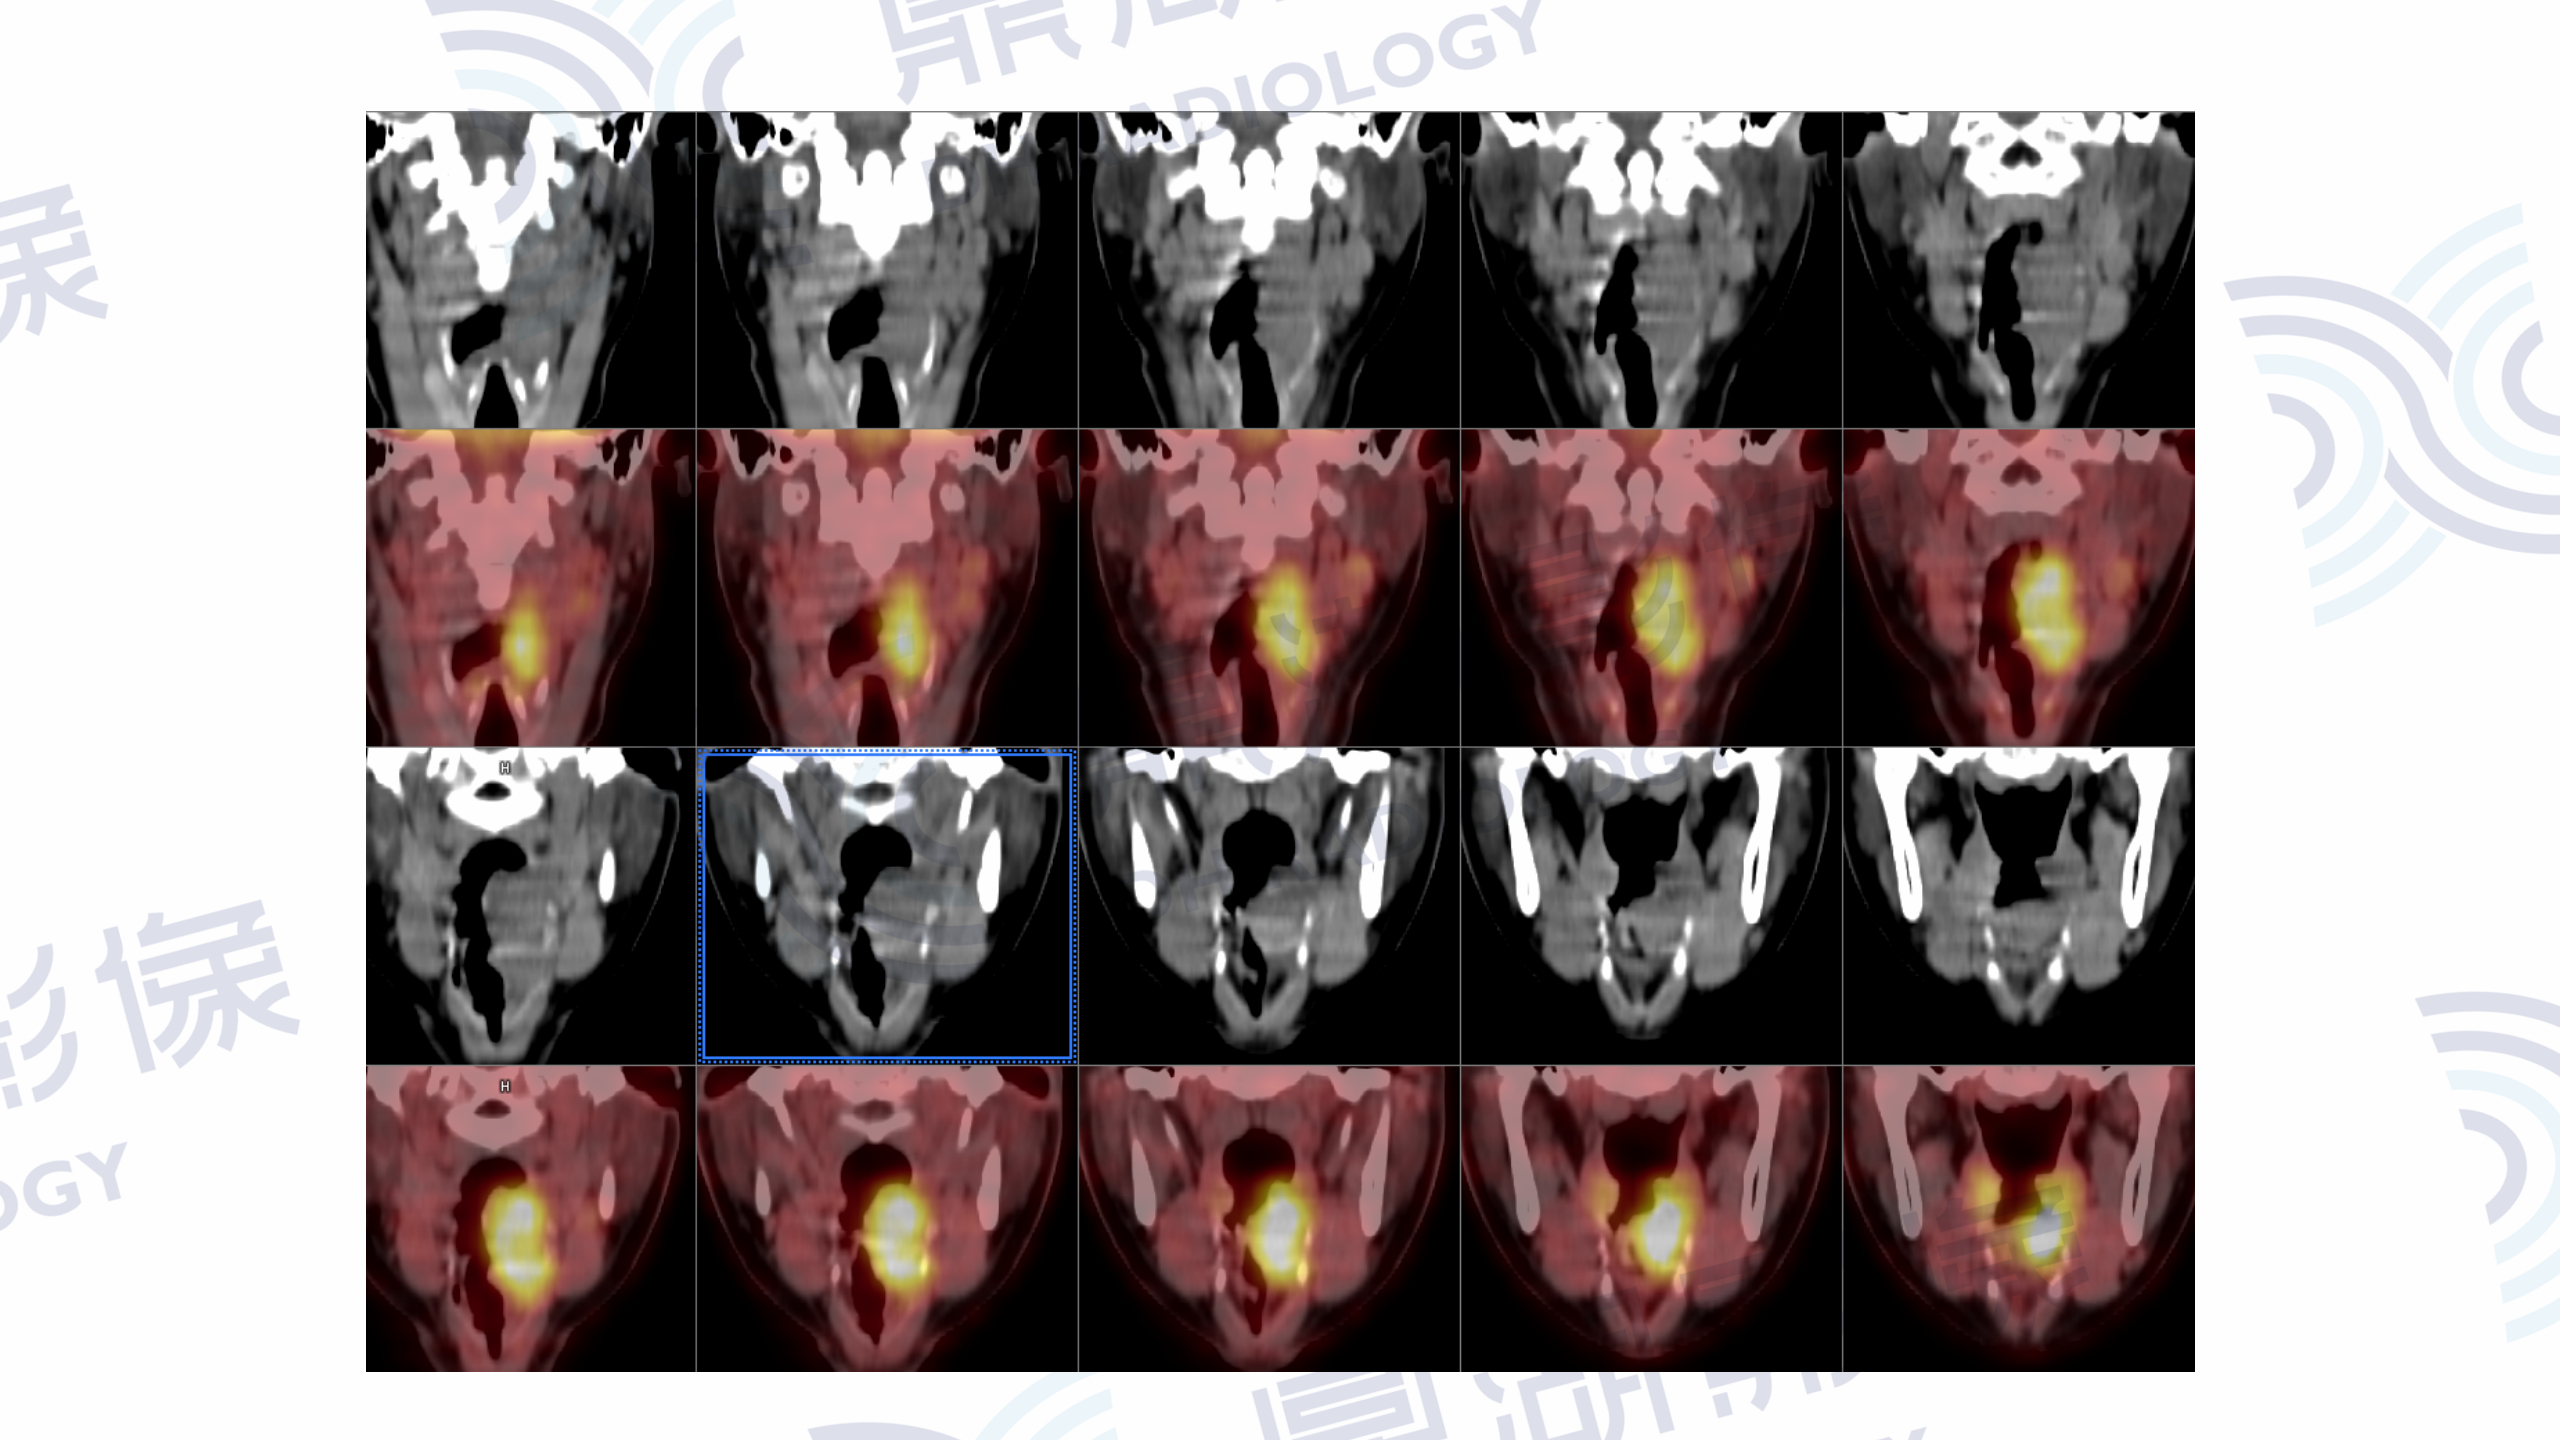

PET/CT提示:口咽左侧壁至左侧声门上软组织肿块,FDG摄取增高,SUVmax=13.1。